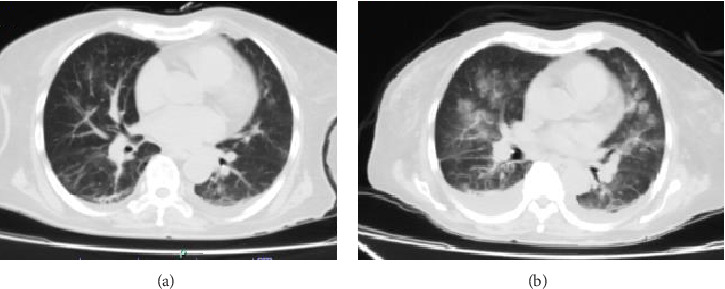

系统性红斑狼疮是一种全身性自身免疫性病理,通常出现在年轻人中,表现为急性,而在50岁以上的人群中,它的晚期表现是罕见的和隐匿的。血管炎是一种影响任何产生纤维蛋白样坏死的血管的病理,表现为抗中性粒细胞细胞质抗体阳性。这两种情况的同时发生是罕见的,并导致较差的临床结果。我们报告了一位73岁的女性患者,她表现为快速进展的肾小球肾炎,需要肾脏替代治疗,肺结核,迟发性红斑狼疮伴狼疮肾炎,中性粒细胞胞浆抗体阳性。活检时发现免疫介导的毛细血管外增生性肾小球肾炎,伴有明显的血管炎征象,在这些实体之间发现重叠综合征。她最初接受抗结核治疗、大剂量甲基强的松龙治疗,并继续接受间歇性肾脏替代治疗;然而,由于他的病情严重,她有了致命的结局。这些自身免疫病变之间的共存是不寻常的;狼疮性肾炎伴髓过氧化物酶-抗中性粒细胞胞浆抗体与少免疫肾小球肾炎之间存在迟发性重叠综合征。双重表现建立临床挑战,其诊断以及免疫抑制治疗的启动时,有额外的感染性病理。

Systemic lupus erythematosus is a systemic autoimmune pathology that generally presents in young people and manifests acutely, while its late presentation in people over 50 years of age is rare and insidious. Vasculitis is a pathology that affects any vessel producing fibrinoid necrosis, and presents with a positive antineutrophil cytoplasmic antibody. The concomitance of these two entities is rare and leads to worse clinical outcomes. We present a 73-year-old female patient who presented with rapidly progressive glomerulonephritis requiring renal replacement therapy, pulmonary tuberculosis, late-onset lupus erythematosus with lupus nephritis, and a positive result for neutrophil cytoplasmic antibody. An immune-mediated extracapillary proliferative glomerulonephritis was found when the biopsy was performed, with obvious signs of vasculitis, an overlap syndrome was found between these entities. She was initially treated with antituberculosis therapy, boluses of methylprednisolone and continued with intermittent renal replacement therapy; however, due to the severity of his pathologies, she had a fatal outcome. The concomitance between these autoimmune pathologies is unusual; there is a late-onset overlap syndrome between lupus nephritis accompanied by myeloperoxidase-antineutrophil cytoplasmic antibody and pauci-immune glomerulonephritis. The dual presentation establishes clinical challenges for its diagnosis as well as the initiation of immunosuppressive therapy when there are additional infectious pathologies.